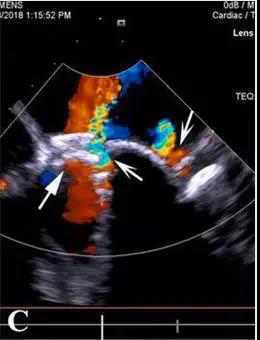

怎么办?再次开胸体外循环手术患者难以耐受,可能意味着死亡,风险更大。而再次经胸封堵术需要去堵“铆钉”间的缝隙,漏口小,对医生的难度大、风险大。有导丝无法通过漏口、捅掉以前植入的封堵器,术后仍然有残余漏、溶血等风险。顶着巨大的压力,李红昕和郭文彬带领的医疗团队经过认真的讨论、分析,决定依据心尖入路比较直的特点,改经左胸-心尖途径去封堵“铆钉”间的缝隙。术中,他们利用自主发明的直中空探条输送系统,成功将导丝送过两个伞盘的间隙,分别再次植入一枚特质封堵器,共4枚,完全封堵住了MPVL。术后患者血红蛋白尿、贫血、黄疸消失,肝肾功能恢复正常,痊愈出院。

经胸MPVL封堵,全部在三维超声引导下操作,解剖图像清晰,患者和医务人员不接触X线和造影剂;中空探条输送系统短,操作灵活,封堵MPVL成功率高。有关该技术的文章已于今年发表于世界顶级心胸外科杂志《Ann Thorac Surg》上。三位患者的成功表明:经右胸或左胸途径微创封堵MPVL能克服传统介入治疗的不同难点,已逐步走向成熟,成为治疗二尖瓣瓣周漏的又一利器,为患者解除了再手术痛苦,为心外科医生解除了后顾之忧。